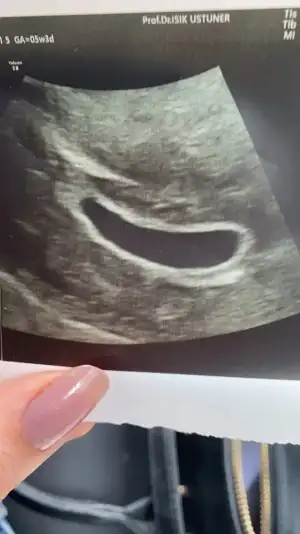

• DC0FC475-7E97-4C6C-8E98-00951B0350F3.webp

DC0FC475-7E97-4C6C-8E98-00951B0350F3.webp

24,5 KB · Görüntüleme: 233

Baya kese büyük canım benim 2 cmlik di senin sanki olacak gibi geliyo bana bebek inşallah olur cnm 8 10 hafta kalp atisi duyulurmus canım senin de embriyo belki olmustur sen ne zmn gitcn kontrole